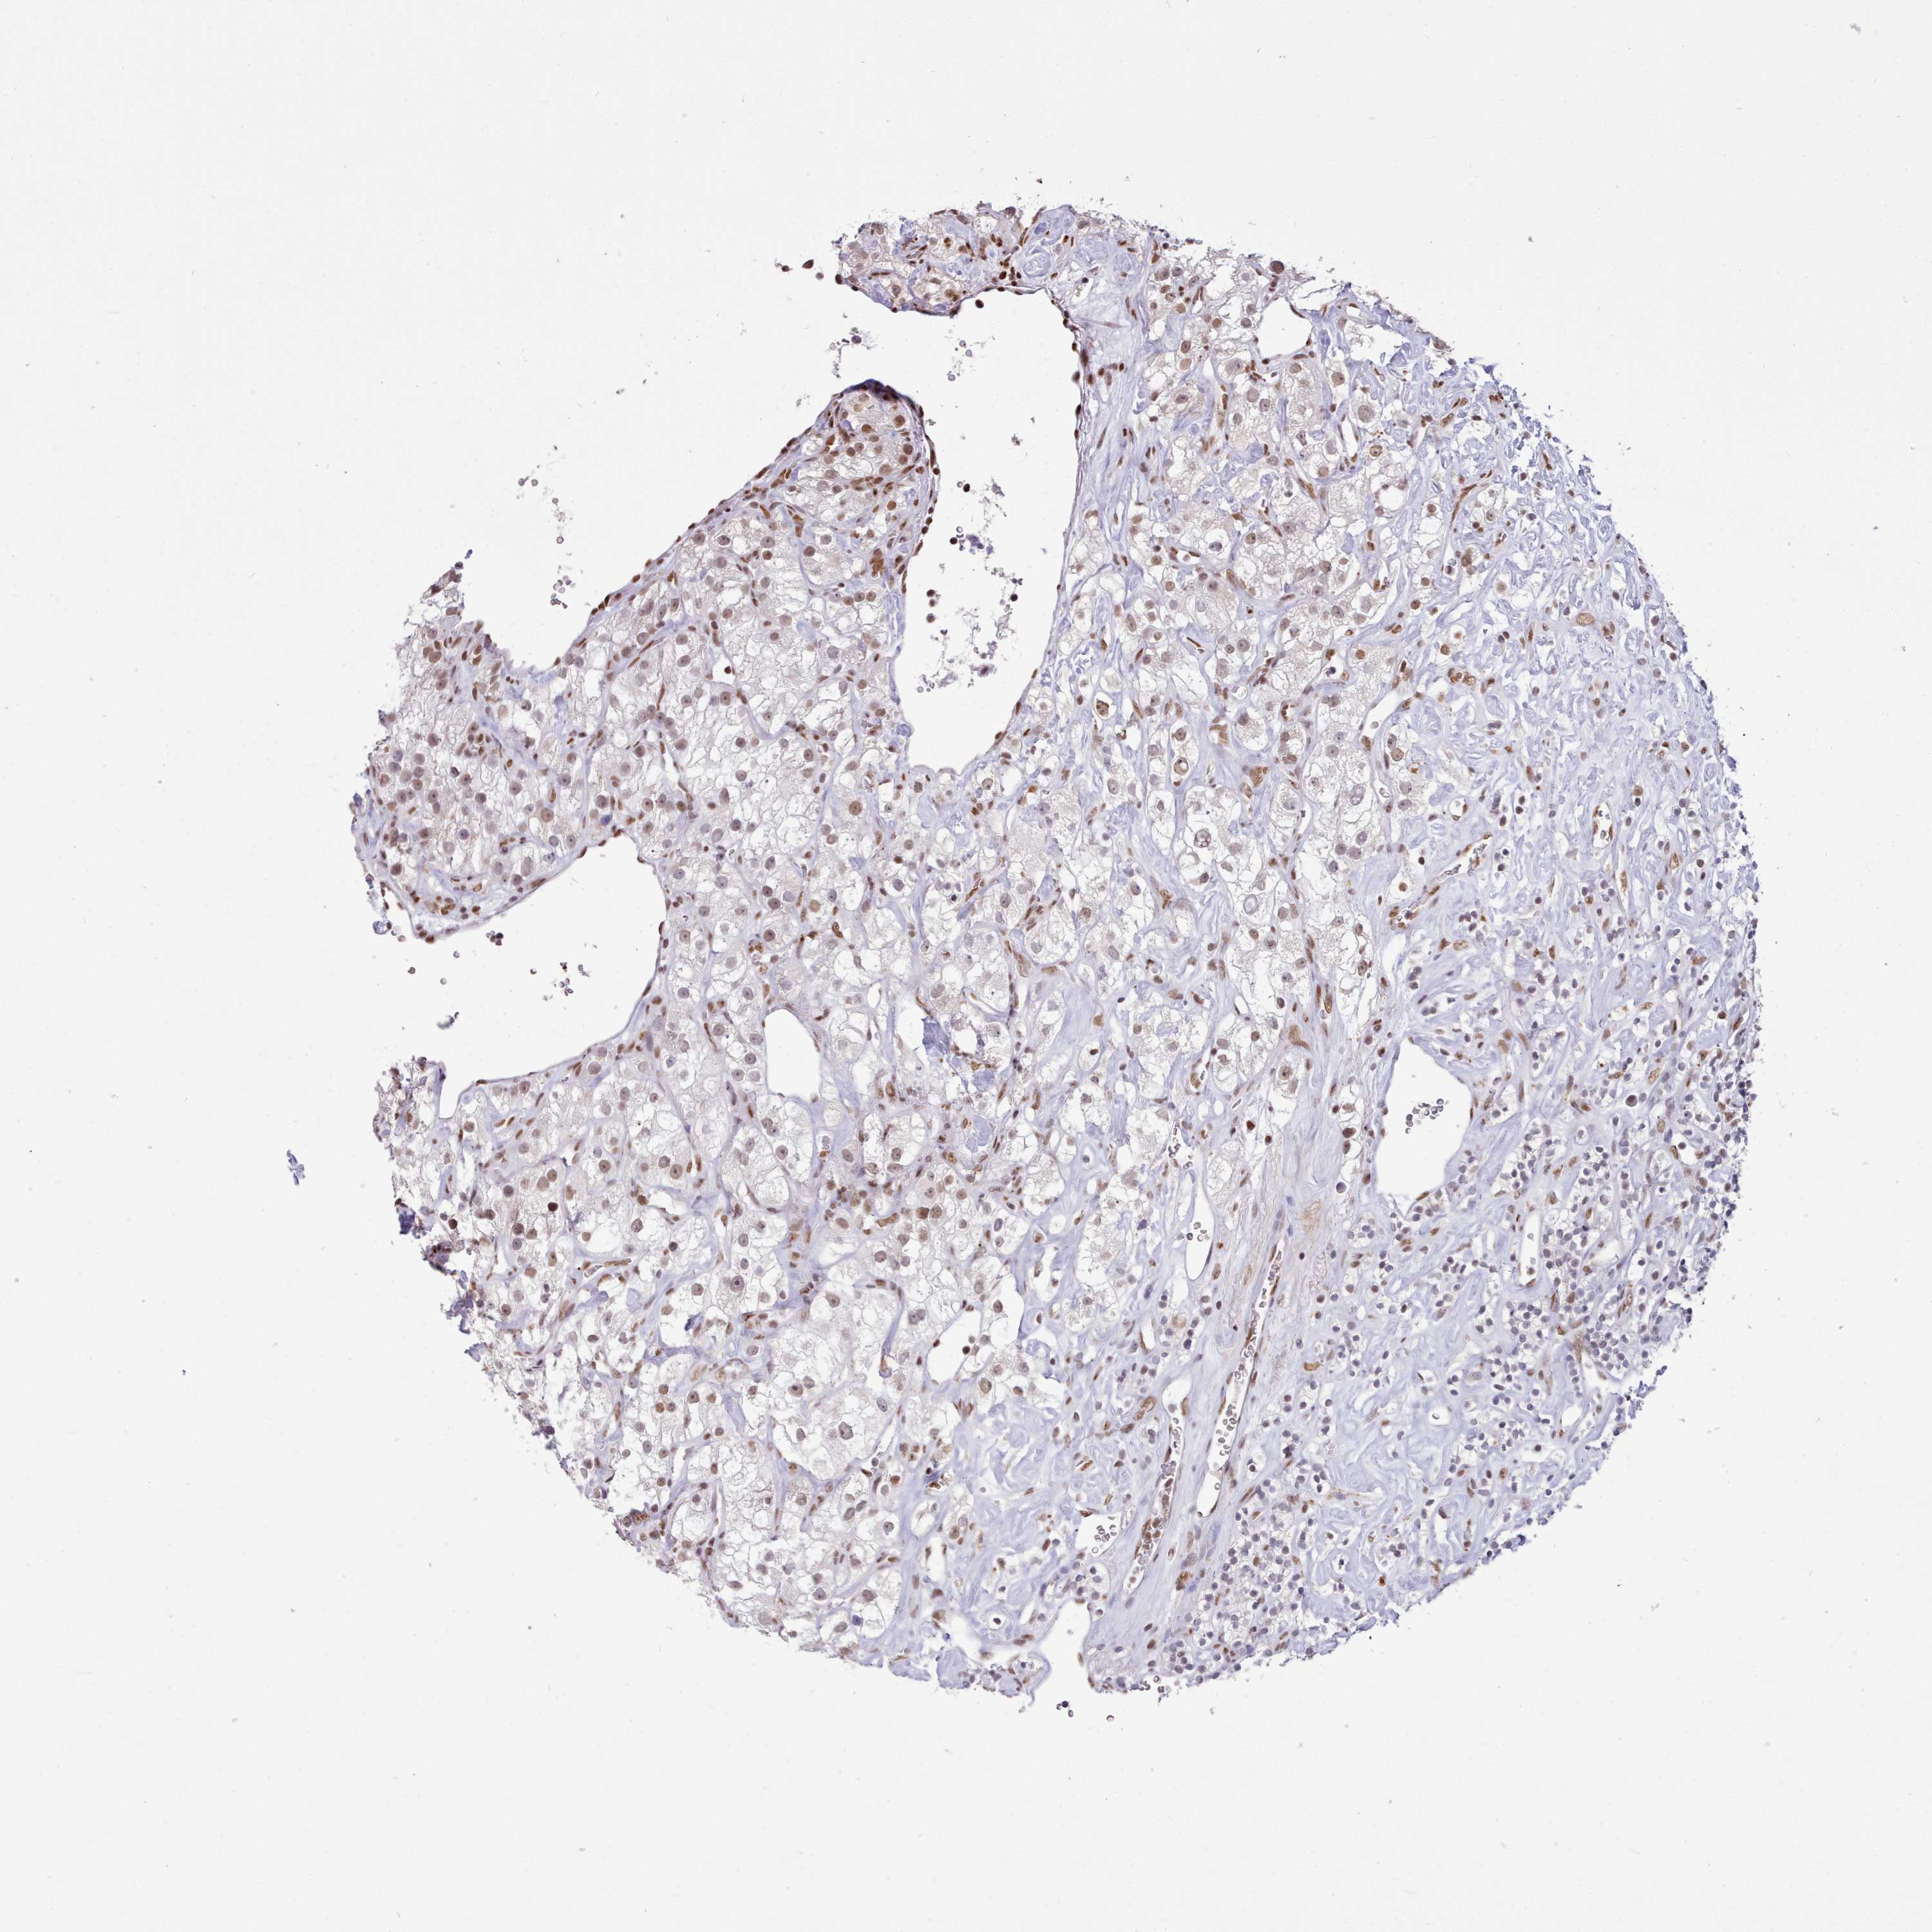

KIDNEY RENAL CLEAR CELL CARCINOMA (VALIDATION) - Interactive survival scatter ploti

The Survival Scatter plot shows the clinical status (i.e. dead or alive) for all individuals in the patient cohort, based on the same data that underlies the corresponding Kaplan-Meier plots. Patients that are alive at last time for follow-up are shown in blue and patients who have died during the study are shown in red.

The x-axis shows the expression levels (FPKM) of the investigated gene in the tumor tissue at the time of diagnosis. The y-axis shows the follow-up time after diagnosis (years). Both axes are complimented with kernel density curves demonstrating the data density over the axes. The top density plot shows the expression levels (FPKM) distribution among dead (red) and alive patients (blue). The right density plot shows the data density of the survived years of dead patients with high and low expression levels respectively, stratified using the cutoff indicated by the vertical dashed line through the Survival Scatter plot. This cutoff is automatically defined based on the FPKM cutoff that minimizes the p-score. The cutoff can be changed by dragging the vertical line or by entering a cutoff value in the square labeled "Current cut-off".

Under the Survival Scatter plot the p-score landscape (black curve; left axis) is shown together with dead median separation (red curve; right axis). Dead median separation is the difference in median mRNA expression between patients who have died with high and low expression, respectively. It is calculated as follows: median FPKM expression of dead patients with high expression - median FPKM expression of dead patients with low expression. This is intended to aid the user in visually exploring custom cutoffs and the associated p-scores and dead median separation.

Individual patient data is displayed and can be filtered by clicking on one or more of the category buttons on the top of the page. Categories describing expression level and patient information include: high, low, alive, dead, female, male and tumor stages. The scale of the x-axis can be toggled between linear and log-scale by clicking on the "x log" button. Mouse-over function shows TCGA ID, patient information and mRNA expression (FPKM) for each patient.

& Survival analysisi

Kaplan-Meier plots summarize results from analysis of correlation between mRNA expression level and patient survival. Patients were divided based on level of expression into one of the two groups "low" (under cut off) or "high" (over cut off). X-axis shows time for survival (years) and y-axis shows the probability of survival, where 1.0 corresponds to 100 percent.

TAF15 is not prognostic in Kidney Renal Clear Cell Carcinoma (validation)

Best expression cut offi

Based on the FPKM value of each gene, patients were classified into two groups and association between prognosis (survival) and gene expression (FPKM) was examined. The best expression cut-off refers the FPKM value that yields maximal difference with regard to survival between the two groups at the lowest log-rank P-value. Best expression cut-off was selected based on survival analysis .

When clicking on this number, the vertical dashed line indicating cut-off, the interactive survival plot, and the Kaplan-Meier curve will be adjusted to show results based on the best expression cut-off.

: 50.99

Median expressioni

Median expression refers to the median FPKM value calculated based on the gene expression (FPKM) data from all patients in this dataset. When clicking on this number, the vertical dashed line indicating cut-off, the interactive survival plot, and the Kaplan-Meier curve will be adjusted to show results based on the median expression.

: N/A

Median follow up timei

Median follow up time refers to the median time (years) after diagnosis with this type of cancer, based on clinical data from all patients in this dataset.

P scorei

Log-rank P value for Kaplan-Meier plot showing results from analysis of correlation between mRNA expression level and patient survival.

N/A

5-year survival highi

5-year survival for patients with higher expression than the expression cutoff.

For melanoma and glioma, 3-year survival is shown.

5-year survival lowi

5-year survival for patients with lower expression than the expression cutoff.

TCGA RNA samplesi

RNA-seq data is reported as average FPKM (number Fragments Per Kilobase of exon per Million reads), generated by the The Cancer Genome Atlas (TCGA) .

Normal distribution across the dataset is visualized with box plots, shown as median and 25th and 75th percentiles. Points are displayed as outliers if they are above or below 1.5 times the interquartile range. FPKM values of the individual samples are presented next to the box plot.

Average pTPM 61.4

Number of samples 100